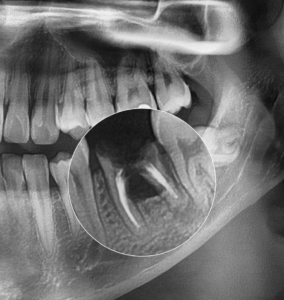

임플란트 를 심고 싶은데 공간이 부족하다면? 비발치 치아 교정

안녕하세요, 교정과 전문의 김정은입니다. ​ 이가 빠지거나 부러졌을 때, “임플란트를 심어야겠다"라는 생각을 하시는 분들이 많습니다. ​ 그런데 실제로 내원해 검사해 보면, 이가 없던 자리에 인접치가 쓰러지거나 공간이 부족해져 있어, 픽스처를…